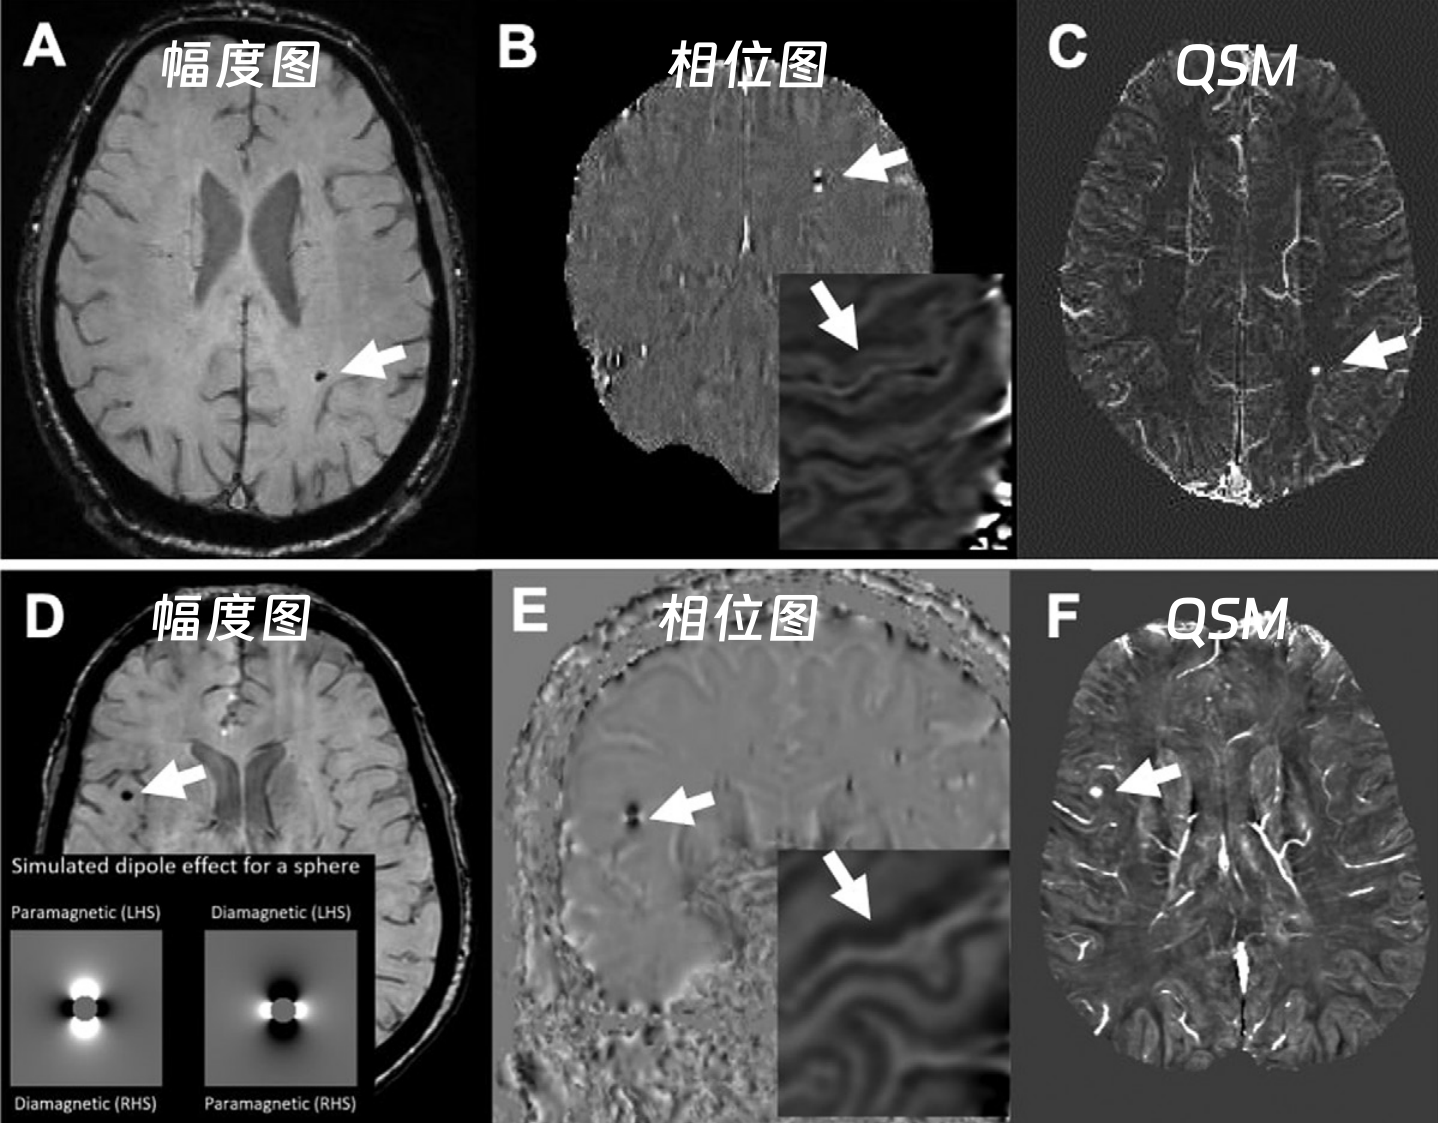

49b3dd764ccd67d6c06a2d54253d9177.png

西门子与GE机器—出血图像对比

(QSM:定量磁化率成像)

在SWI图像判断时,西门子设备上钙化在相位图呈低信号,而GE、飞利浦上呈高信号,这是因为不同厂商采用的相位坐标系统不同

不同厂商磁共振设备的SWI相位图信号差异,源于相位坐标系的左右手系统区别:

01

右手坐标系(飞利浦、GE)

坐标特性:顺磁性物质产生负相移,相移越大相位图越亮(灰度越高)。

信号表现:

出血(顺磁性):相位图呈低信号,幅度图及 MIP 图呈低信号。

钙化(抗磁性):相位图呈高信号,幅度图及 MIP 图呈低信号。

物质判断:

若幅度图 / MIP 图为低信号,且相位图为高信号→ 抗磁性物质(如钙化)。

若幅度图 / MIP 图为低信号,且相位图为低信号→ 顺磁性物质(如铁沉积、钆沉积、出血)。

02

左手坐标系(西门子、佳能)

坐标特性:顺磁性物质产生正相移,相移越大相位图越亮(灰度越高)。

出血(顺磁性):相位图呈高信号,幅度图及 MIP 图呈低信号。

钙化(抗磁性):相位图呈低信号,幅度图及 MIP 图呈低信号。

若幅度图 / MIP 图为低信号,且相位图为高信号→ 顺磁性物质(如铁沉积、钆沉积、出血)。

若幅度图 / MIP 图为低信号,且相位图为低信号→ 抗磁性物质(如钙化)。